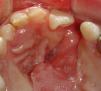

Presentación del casoSe trata de paciente femenino de 5 años de edad, referida a nuestro servicio bajo el diagnóstico de fístula oronasal. Entre sus antecedentes encontramos que se le realizó queiloplastía bilateral y palatoplastía del paladar blando a la edad de 6 meses y palatoplastía del paladar duro a los 4 años, presentando en este último procedimiento una dehiscencia (fístula oronasal) que provocaba rinofonía y reflujo nasal de los alimentos. En la exploración intraoral observamos una fístula oronasal en la unión del paladar primario y secundario del lado izquierdo de aproximadamente 12mm x 25mm (fig. 1).